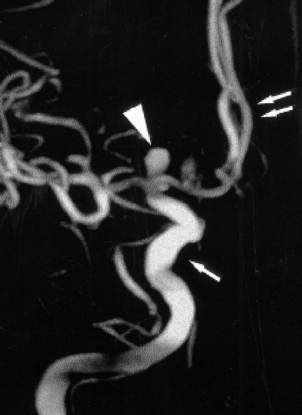

Saccular aneurysms are usually sited at proximal branching points on the anterior portion of the circle of Willis, particularly on the internal carotid, anterior communicating and middle cerebral arteries. Most are less than 10mm in diameter, but some may be partly filled by thrombus, which can obscure their true size on radiological studies (Fig. 26.12). Their pathogenesis is thought to relate to congenital defects in the smooth muscle of the tunica media at the site of an arterial bifurcation, where local haemodynamic factors act to produce a slowly enlarging aneurysm.

image

Fig. 26.12 Demonstration of a saccular aneurysm in vivo. This 3D digital subtraction angiogram shows a large grape-like saccular aneurysm (arrowhead) arising at the terminal region of the internal carotid artery (single arrow). The anterior cerebral arteries (double arrows) appear normal.

(Courtesy of Dr D Summers, Edinburgh.)